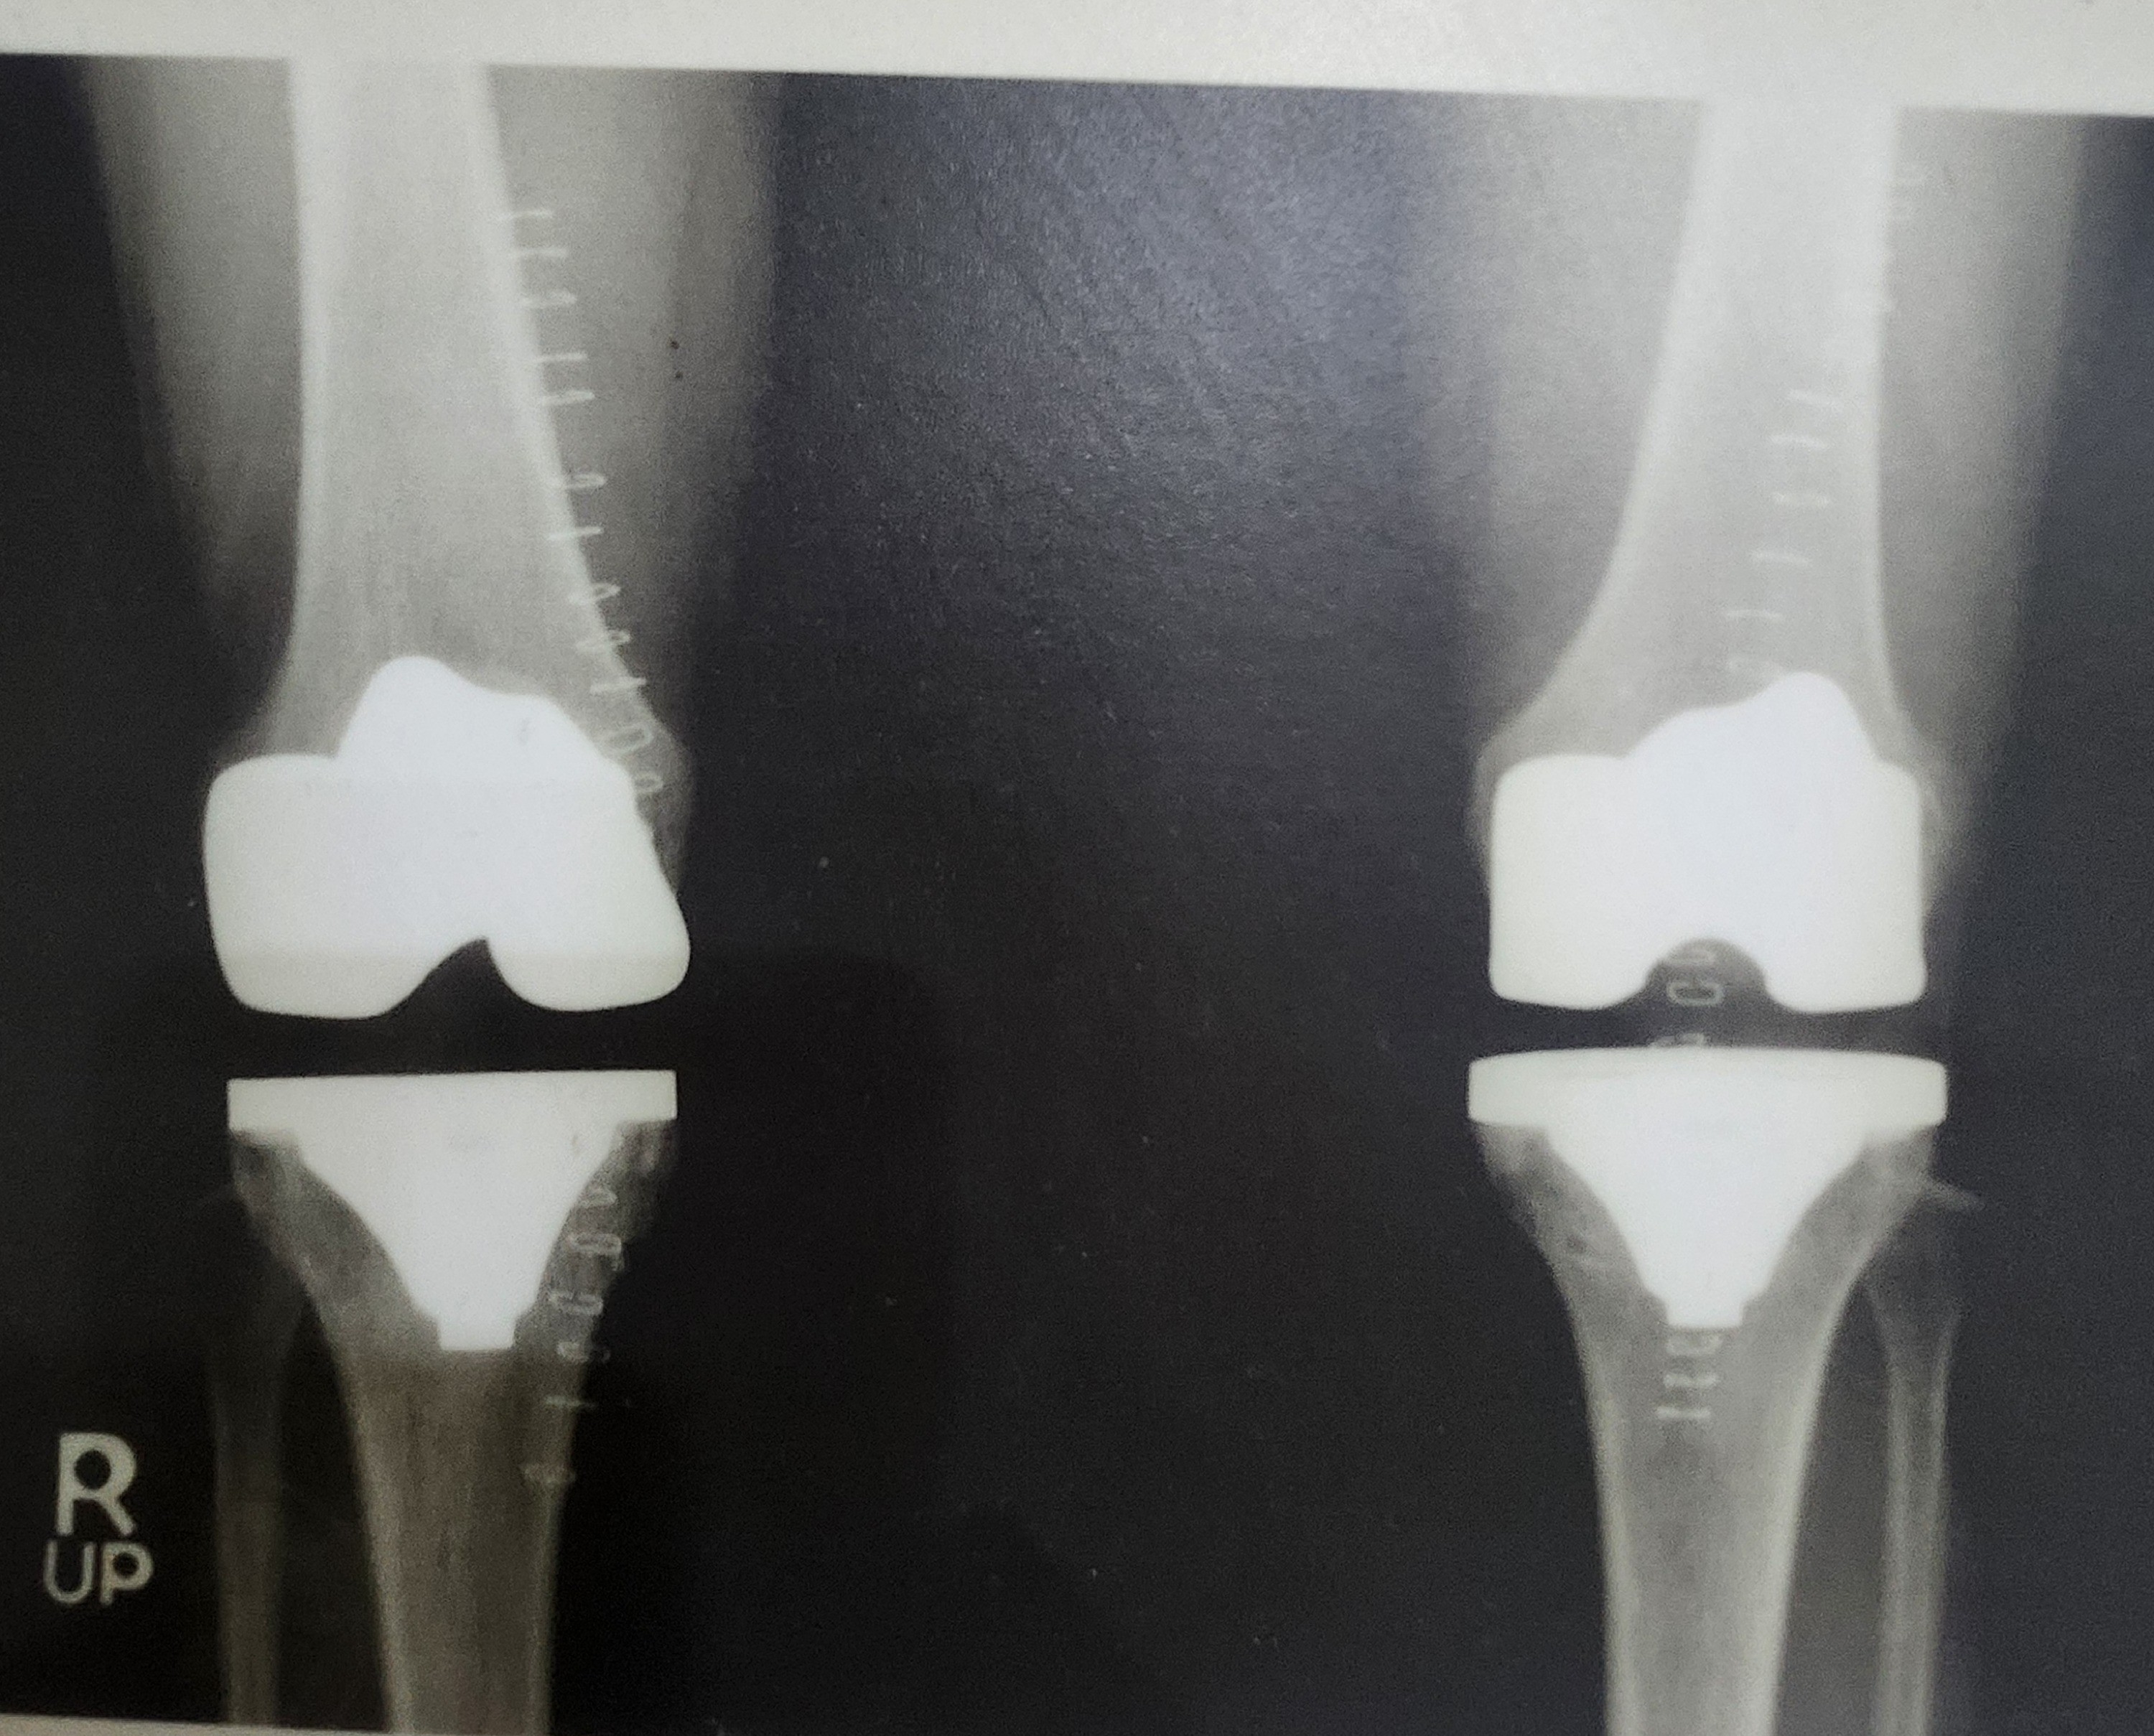

인공관절 클리닉

모세정형외과의 인공관절 클리닉은 최첨단 장비와 최신 의료기술로 전문적으로 진단하고 환자의 상태에 따라 맞춤형 치료 방법을 제공합니다.